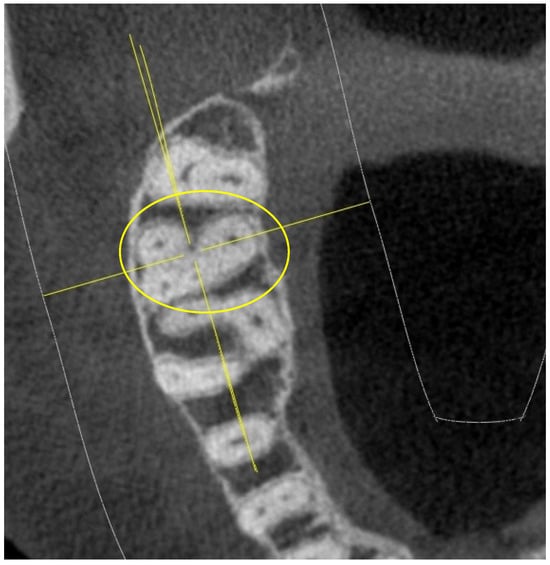

- shape of the pulp chamber associated with a letter of the alphabet (in relation to the number and arrangement of canal orifices);

- K: in maxillary molars with the presence of four canal orifices: MB, MB-2, disto-buccal and palatal; a line joining the disto-buccal and palatal and two other lines radiating from the center of this line to MB and MB-2, forming the letter “K” of the alphabet.

- Y: in maxillary molars with three canal orifices: MB, disto-buccal and palatal; when a line is formed joining the three canals in the center of the access cavity, it resembles the letter “Y” of the alphabet.